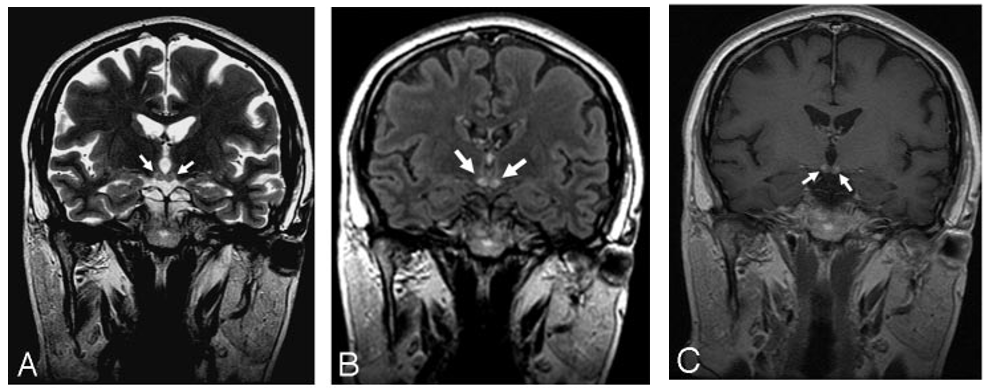

这是由于维生素B1缺乏引起的中枢神经系统代谢性脑病,酗酒是最常见的诱发因素。临床以精神症状、眼肌麻痹和共济失调三主征为主要表现,MRI异常信号围绕第三/第四脑室和导水管。最常受累的结构为乳头体,见于80%的韦尼克脑病患者。如果丘脑背内侧受累,常伴有记忆力障碍。

颅脑MRI冠状位示:双侧乳头体高信号

增强扫描示:双侧乳头体中心强化